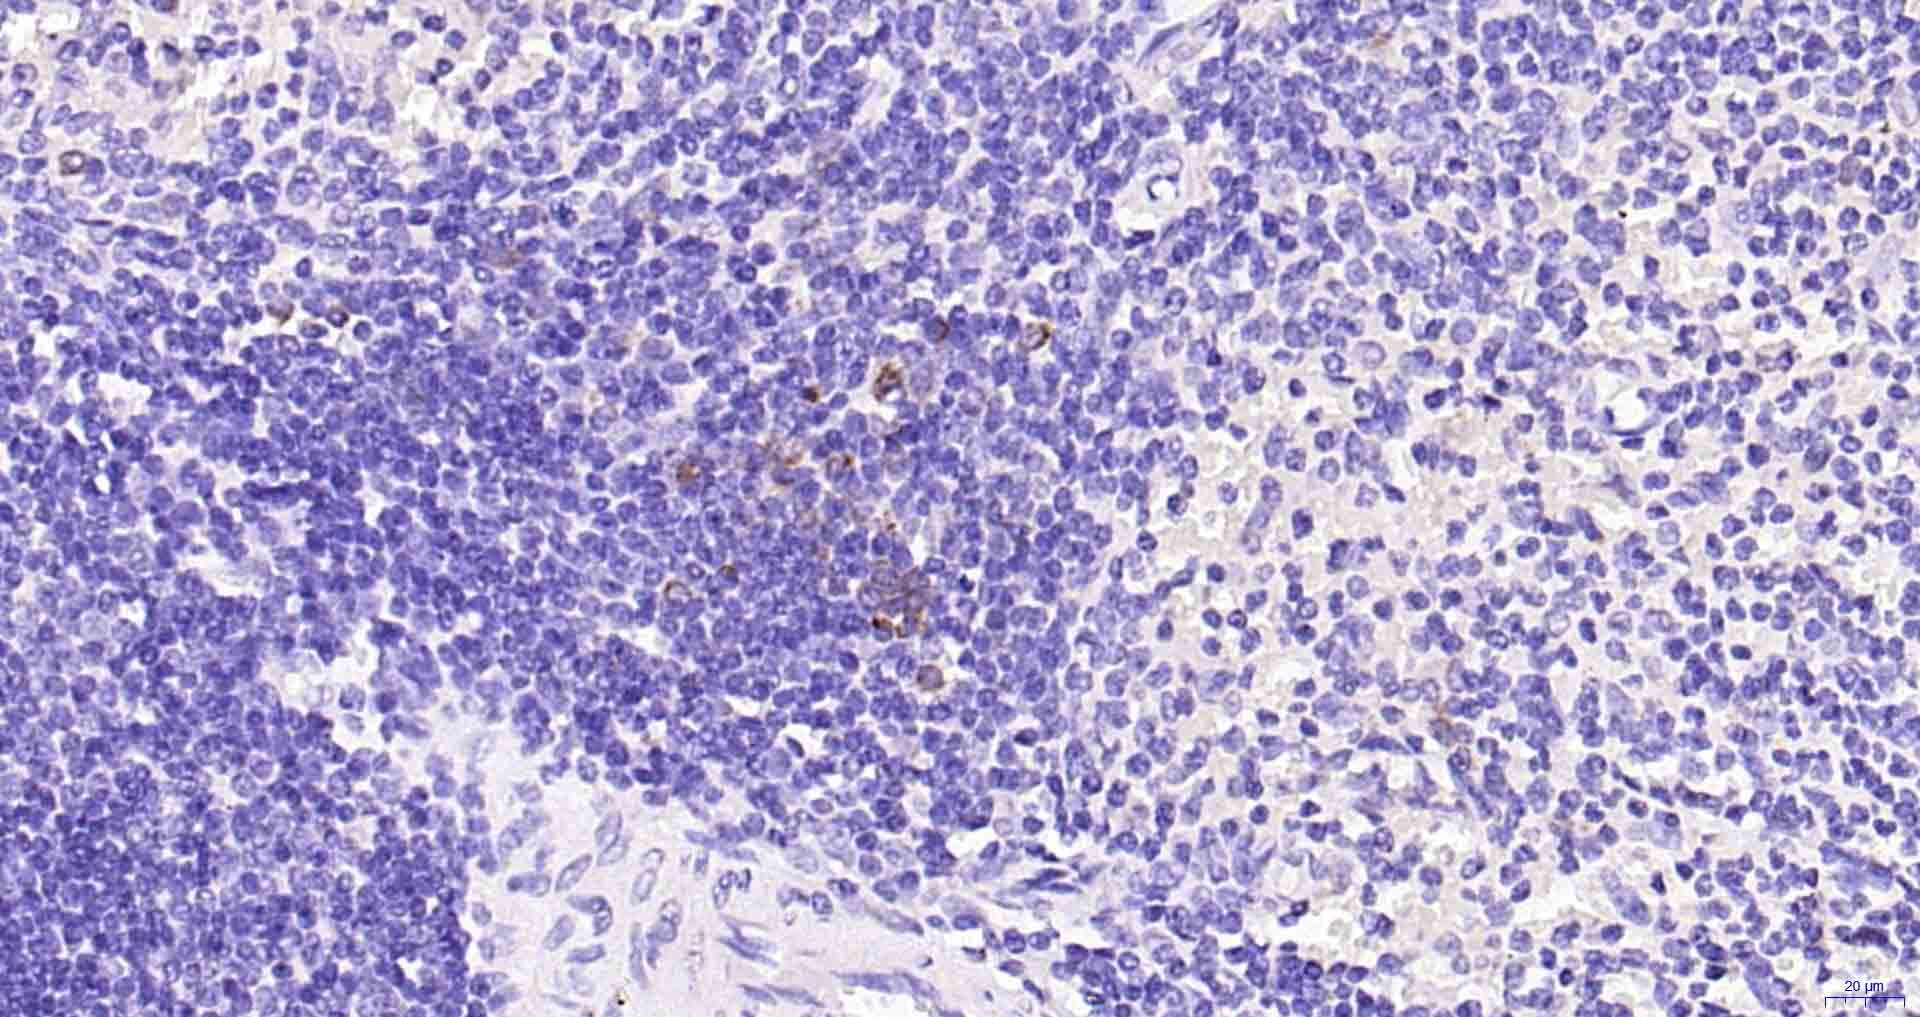

• IHC-P

• IHC-F

IHC-P IHC-P1:50-200

IHC-F IHC-F1:50-200